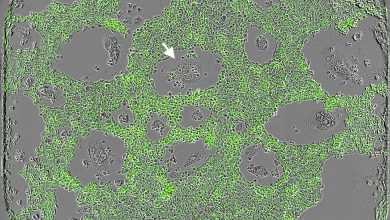

Uma cocultura de macrófagos (seta branca, sem rótulo, por exemplo) mastigando uma população de células de câncer de pulmão mutantes…